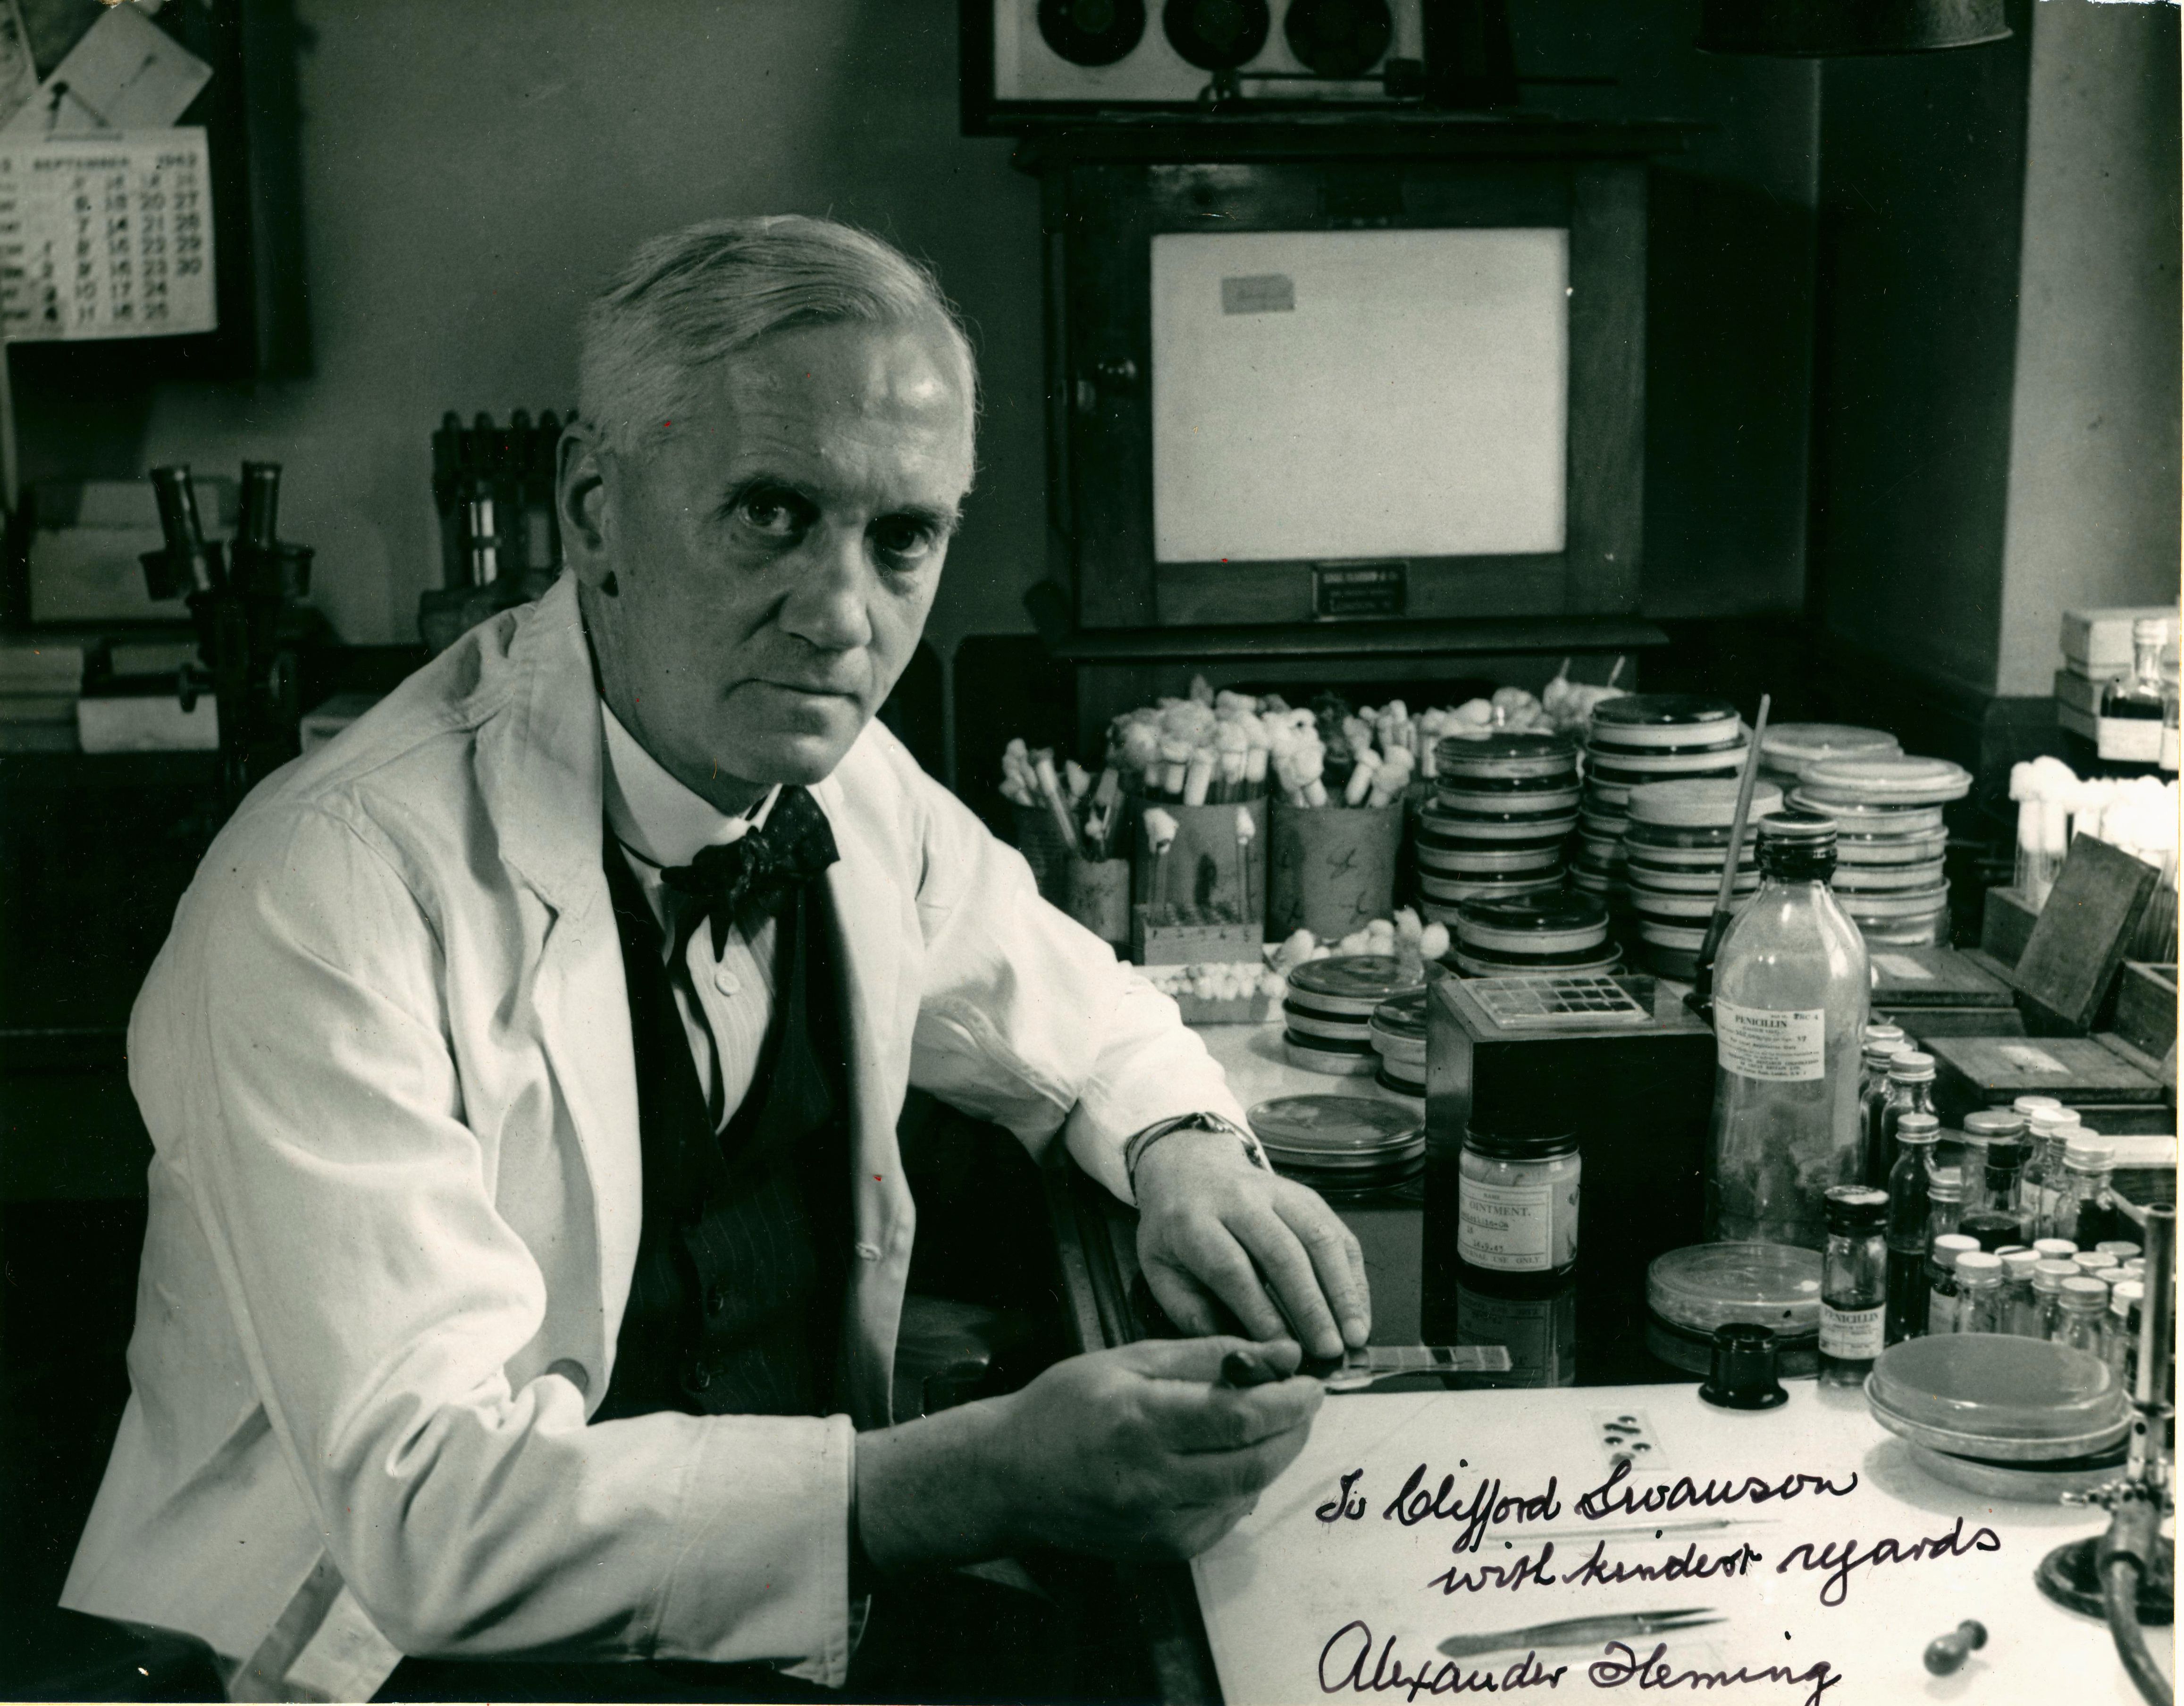

Penicillin: When Contamination Became a Miracle

In 1928, Alexander Fleming returned from vacation to find his laboratory in London contaminated with mold growing in a petri dish of Staphylococcus bacteria cultures. Instead of simply discarding the spoiled sample, Fleming noticed something extraordinary: bacterial colonies would not grow near the mold.

The mold, Penicillium notatum, was releasing a substance that killed harmful bacteria. That substance became penicillin, the first true antibiotic that changed medicine forever, leading to treatments for pneumonia, syphilis, strep throat, and more. What started as an accident on a dirty dish turned into a discovery that has saved over 200 million lives.